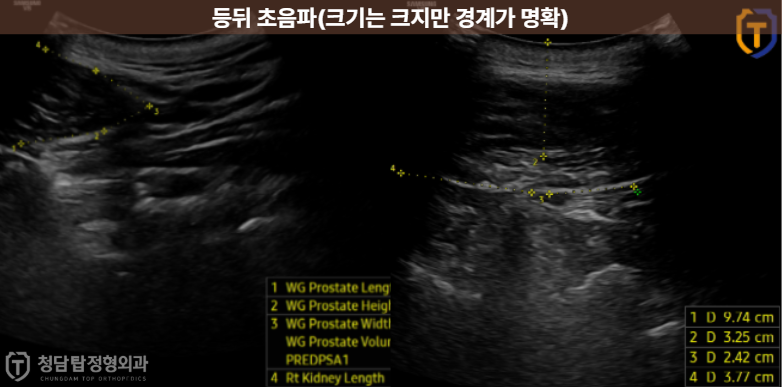

반면 등에 커다란 혹이 있었던 30대 환자분은 특별한 통증 없이 크기만 커지는 전형적인 ‘지방종’이였습니다.

등에 10cm 크기의 거대 지방종이 있던 30대 환자분처럼,

몸에 혹의 크기가 커지면서 피부가 당기고 불편감이 느껴질 때는

일상생활의 질을 높이기 위해 수술을 결정하는 좋은 기준이 될 수 있습니다.

초음파 진단: 혹의 정확한 크기와 깊이, 주변 조직과의 관계를 파악합니다.